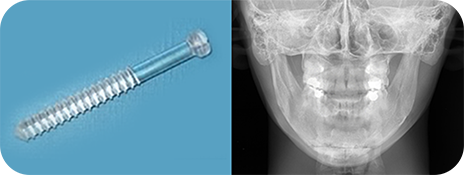

V라인 고정방식

-

일반 티타늄 고정핀

브이라인수술시 앞턱에 고정되는 핀

통상적으로 사용하는 티타늄소재의 고정핀은 인체에는 무해하지만 엑스레이 상 육안으로 확인되는 단점이 있습니다

-

흡수성 핀

뼈를 고정하기 위한 흡수성 핀

뼈가 붙은 이후 1년 내외로 사라지게 되어 엑스레이 상에서 흔적을 남기지 않는걸 원하시는 분에게 적합한 수술법입니다

VS